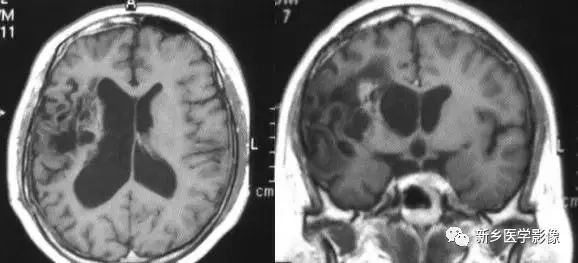

2.一侧大脑半球萎缩

可由许多原因引起,如脑梗死、外伤、出血及感染等。最常见的原因是血管闭塞引起大面积脑。CT和MRI现为患侧侧脑室扩大、脑组织量减少,中线向患侧移位,严重者脑沟和脑回消失不见。

3.脑三叉神经血管瘤病

又称为脑颜面血管瘤综合征,CT平扫以一侧半球脑实质内脑回样、轨道样、弧带状或锯齿状钙化为特征。由于受累侧血供障碍,常引起脑实质萎缩.所以可以表现有患侧侧脑室扩大,颅腔变小,颅板增厚。脑内典型钙化及临床三叉伸经分布区有紫红色血管痣。